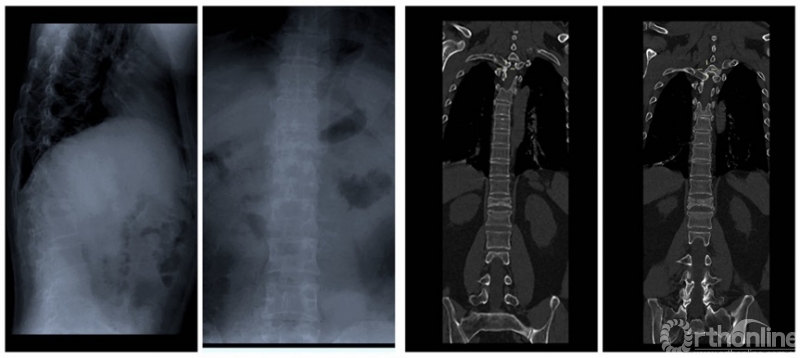

CT提示:肺部磨玻璃样改变;胸12、腰1骨折。核磁共振提示:胸12、腰1压缩性骨折。咽拭子核酸检测阳性。

术前影像学检查

在病情分析会上,会诊医生团队发现患者新冠肺炎的症状并不严重,没有发热,只有咳嗽,且肺部磨玻璃改变范围较为局限,但他的胸腰椎骨折压缩很严重,核磁共振显示椎管侵占已经超过50%,而且有明确的脊髓损伤不全瘫的表现,双下肢肌力均不到2级,感觉严重减退,大小便均失去控制,需要进行抢救性手术治疗。

术后脊柱固定情况